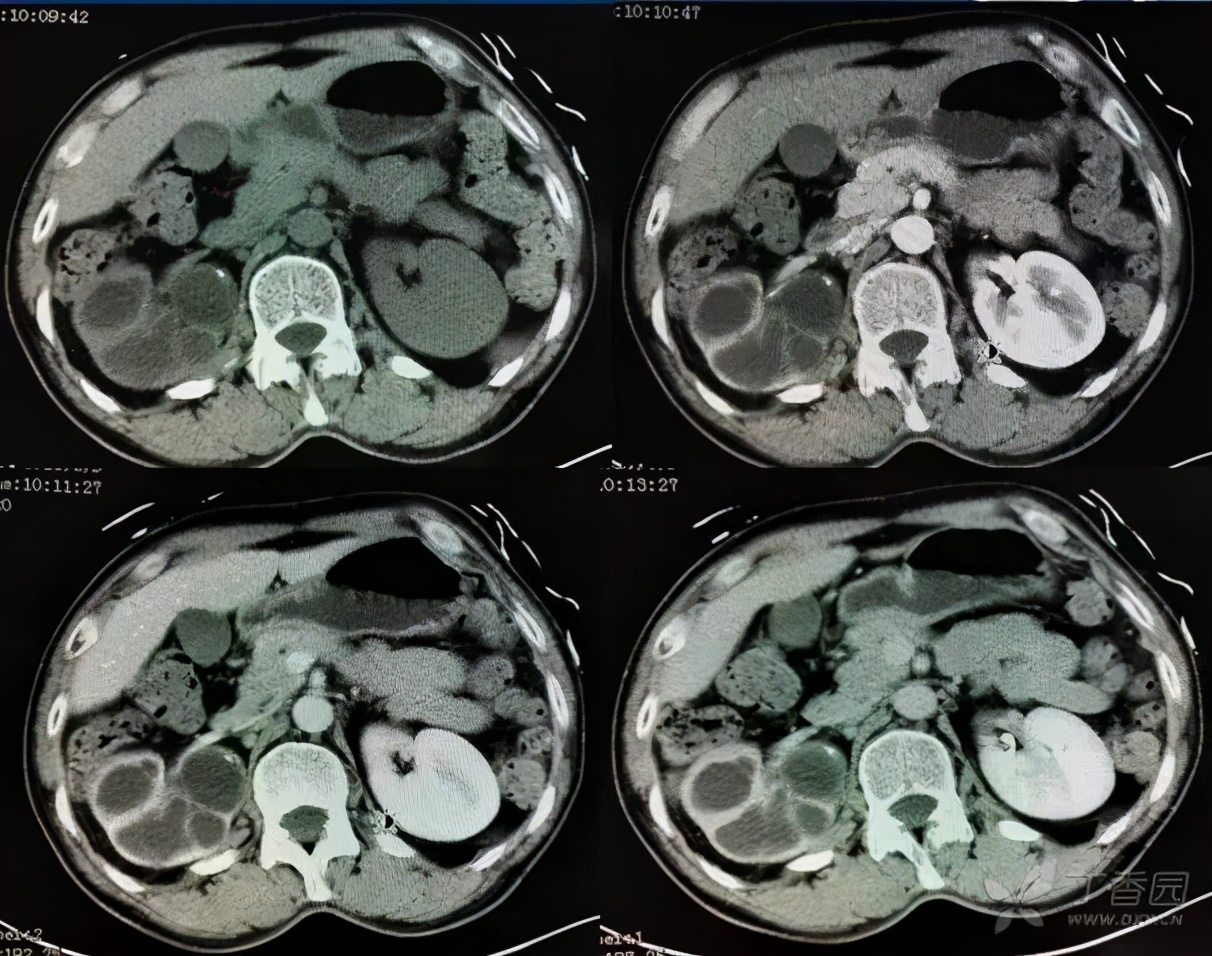

泌尿系结核、肾结核,真的不是那么容易做出诊断的。当怀疑是结核时,就需要反复留取尿液看看能否抓到证据,最直接的证据就是尿结核杆菌培养阳性。但是结核杆菌的培养和普通细菌培养不同,阳性率低。除此之外,还有一些其他的简介证据,比如结核菌素实验、结核抗体、结核T细胞免疫反应实验等等。除此之外,影像学检查也是非常重要,肾结核最典型的表现是“调色板”样的改变。